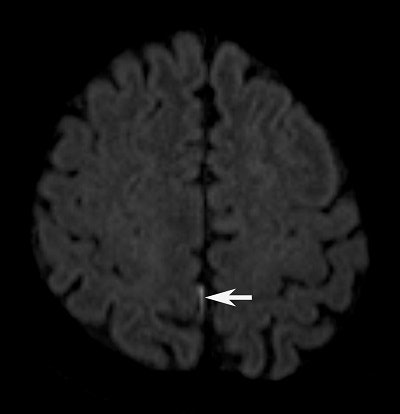

DWI pinpoints a tiny hyperintensity spot (arrow) in the posterior right fissure. Image courtesy of Dr. C.C. Tchoyoson Lim.DWI also found uncommon hyperintensities in the cerebellum of five patients, detecting lesions as small as 7 mm and as large as 42 mm. Interestingly, lesions in the brain parenchyma, subarachnoid space, ventricles, and cerebellum were not visible on T2-weighted or FLAIR images or with the addition of contrast.